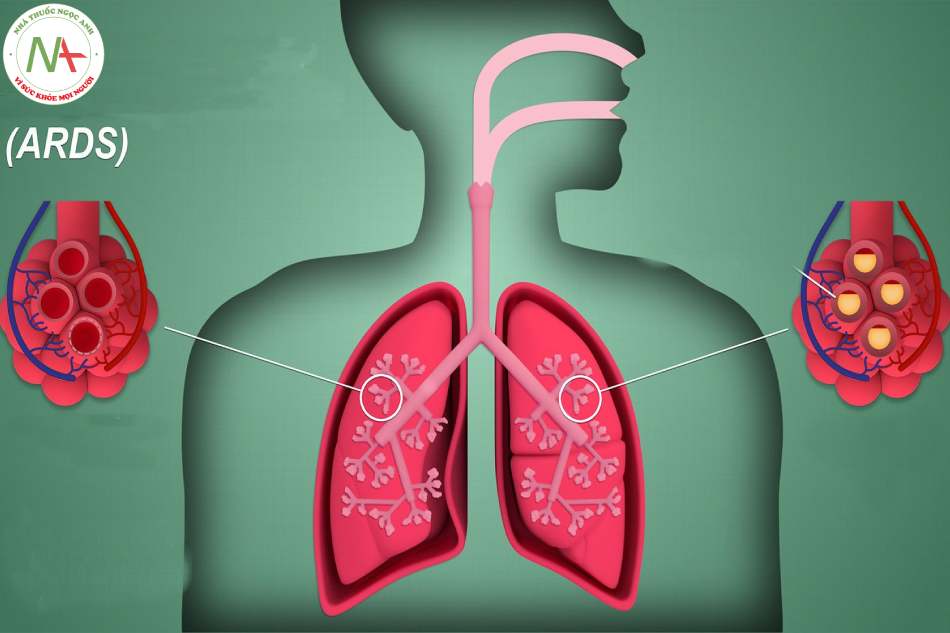

Hội chứng suy hô hấp cấp tiến triển (ARDS) được Ashbaugh và cộng sự mô tả lần đầu tiên năm 1967. Là một hội chứng bệnh lý trong đó màng phế nang mao mạch của phổi bị tổn thương cấp tính do nhiều nguyên nhân khác nhau dẫn đến tình trạng suy hô hấp nặng không đáp ứng với thở oxy liều cao.

- Khó thở, tím môi và đầu chi, thở nhanh. Nghe phổi có ran nổ lan tỏa.

- Xét nghiệm khí máu: PaO2 giảm, thường có giảm CO2 kèm theo (kiềm hô hấp), tăng chênh lệch (gradient) oxy động mạch – mao mạch.

- Xquang phổi: hình ảnh thâm nhiễm lan tỏa 2 phổi.

- Hình ảnh chụp cắt lớp vi tính ngực: tổn thương thâm nhiễm lan tỏa 2 phổi.